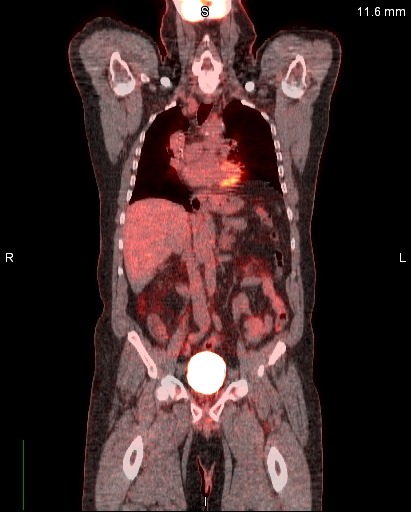

Dec. 2019 Lymph PET/CT Scan - 12-11-2019 @ JW_HW

PT SCAN HISTORY

12-11-2019

4/2/2020 - 9/23/2020

(Treatment Working)

Body_PT_(CT)_Scan Pre-Treatment CT Scan

Pre / Post Reports

Body_PT (CT)_Scan_Report

(Pre Infusion)

January 29, 2020

Body_PT_(CT)_Scan_Report

(Post Infusion)

April 1, 2020

#2- Body_PT_(CT)_Scan

Sep. 23, 2020